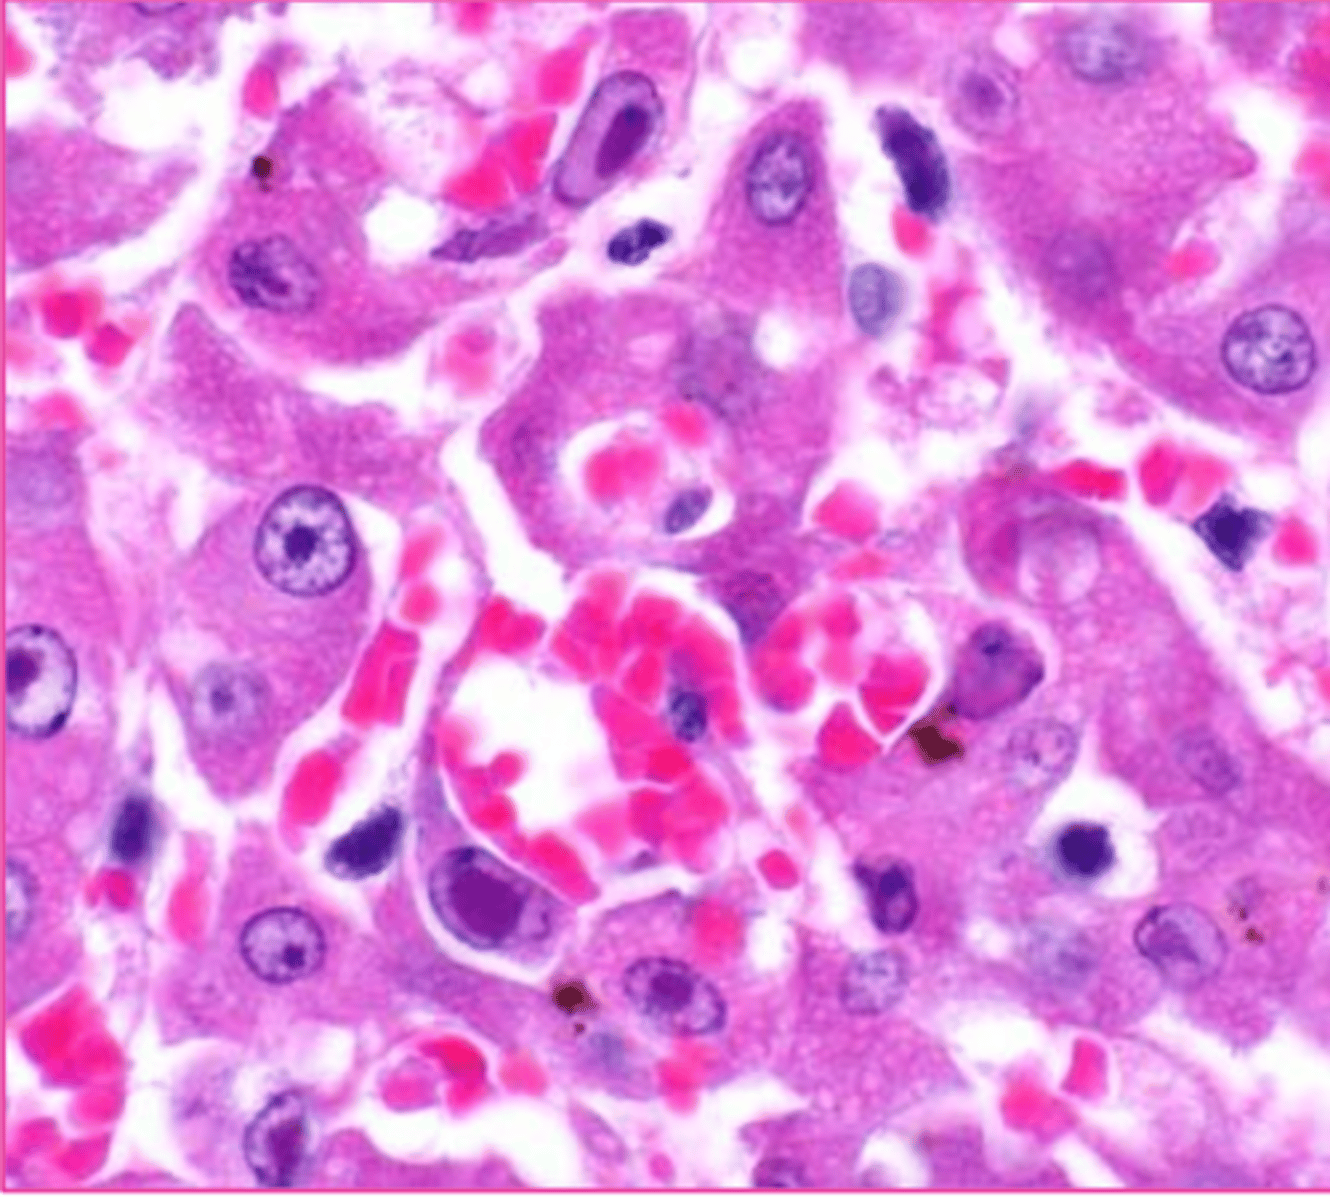

hyaline droplet

these are renal tubular epithelial cells... what is circled?

what are these bright esosinophilic 'dip dops'